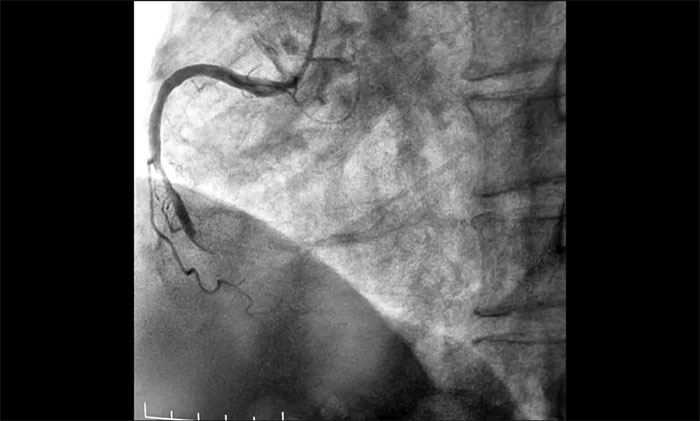

近日,上海蓝十字脑科医院为一名急性心梗患者实施介入手术。该患者因“间断心前区不适伴咽部束缚感7小时,全身乏力3小时”入院,综合其病史和相关检查确诊其为急性下壁心肌梗死,随时有猝死风险,手术指征明确。经球囊扩张和支架置入,开通闭塞血管,助其恢复心肌供血。

▲ 术前,前降支、回旋支、右冠状动脉严重狭窄及完全闭塞

▲ 术后,血管顺利开通